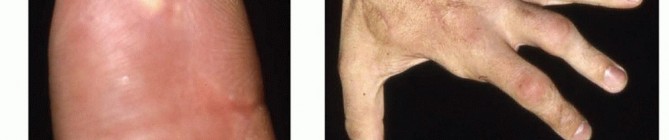

Injuries caused by high-pressure injection equipment, which can generate pressures of 2000 to 12,000 pound per square inch (psi),9 are more than sufficient force to break the skin.15 Substances typically injected include grease, paint, paint thinners, diesel fuel, oil, water, and cement. Cases involving molten metal,3 dry cleaning solvents,11 and veterinary vaccines5 have also been documented.Hallmark of injury is an innocuous-appearing superficial wound that can greatly underestimate the true extent of injury (FIG 1).The three most important determinants of morbidity are the (1) type of substance injected, (2) anatomic location of injury, and (3) delay in treatment.Treatment of injection injuries is urgent and thorough surgical débridement.High-pressure injection injuries occur most frequently in young men, particularly among those who are manual laborers.Previously, it was thought that most of these injuries occurred to people who had been on the job for less than 6 months, but more recent studies show that the mean time on the job was 11 years.12,32Typical scenarios include grasping pressurized tubing in which there is a break in the seal or attempting to unclog the nozzle of a high-pressure injector with the guard removed (FIG 2).With the increasing use of power contrast injection in computed tomography (CT), contrast extravasation injuries may be classified under injection injuries of the upper extremity. However, the pressures involved are generally much lower (100 psi),33 the associated injuries are more proximal, and the natural history isgenerally benign, with surgery rarely being required. FIG 1 • An innocuous-appearing puncture of the volar radial surface of the right small finger. This may be the only visible point of injury in a high-pressure injection injury.